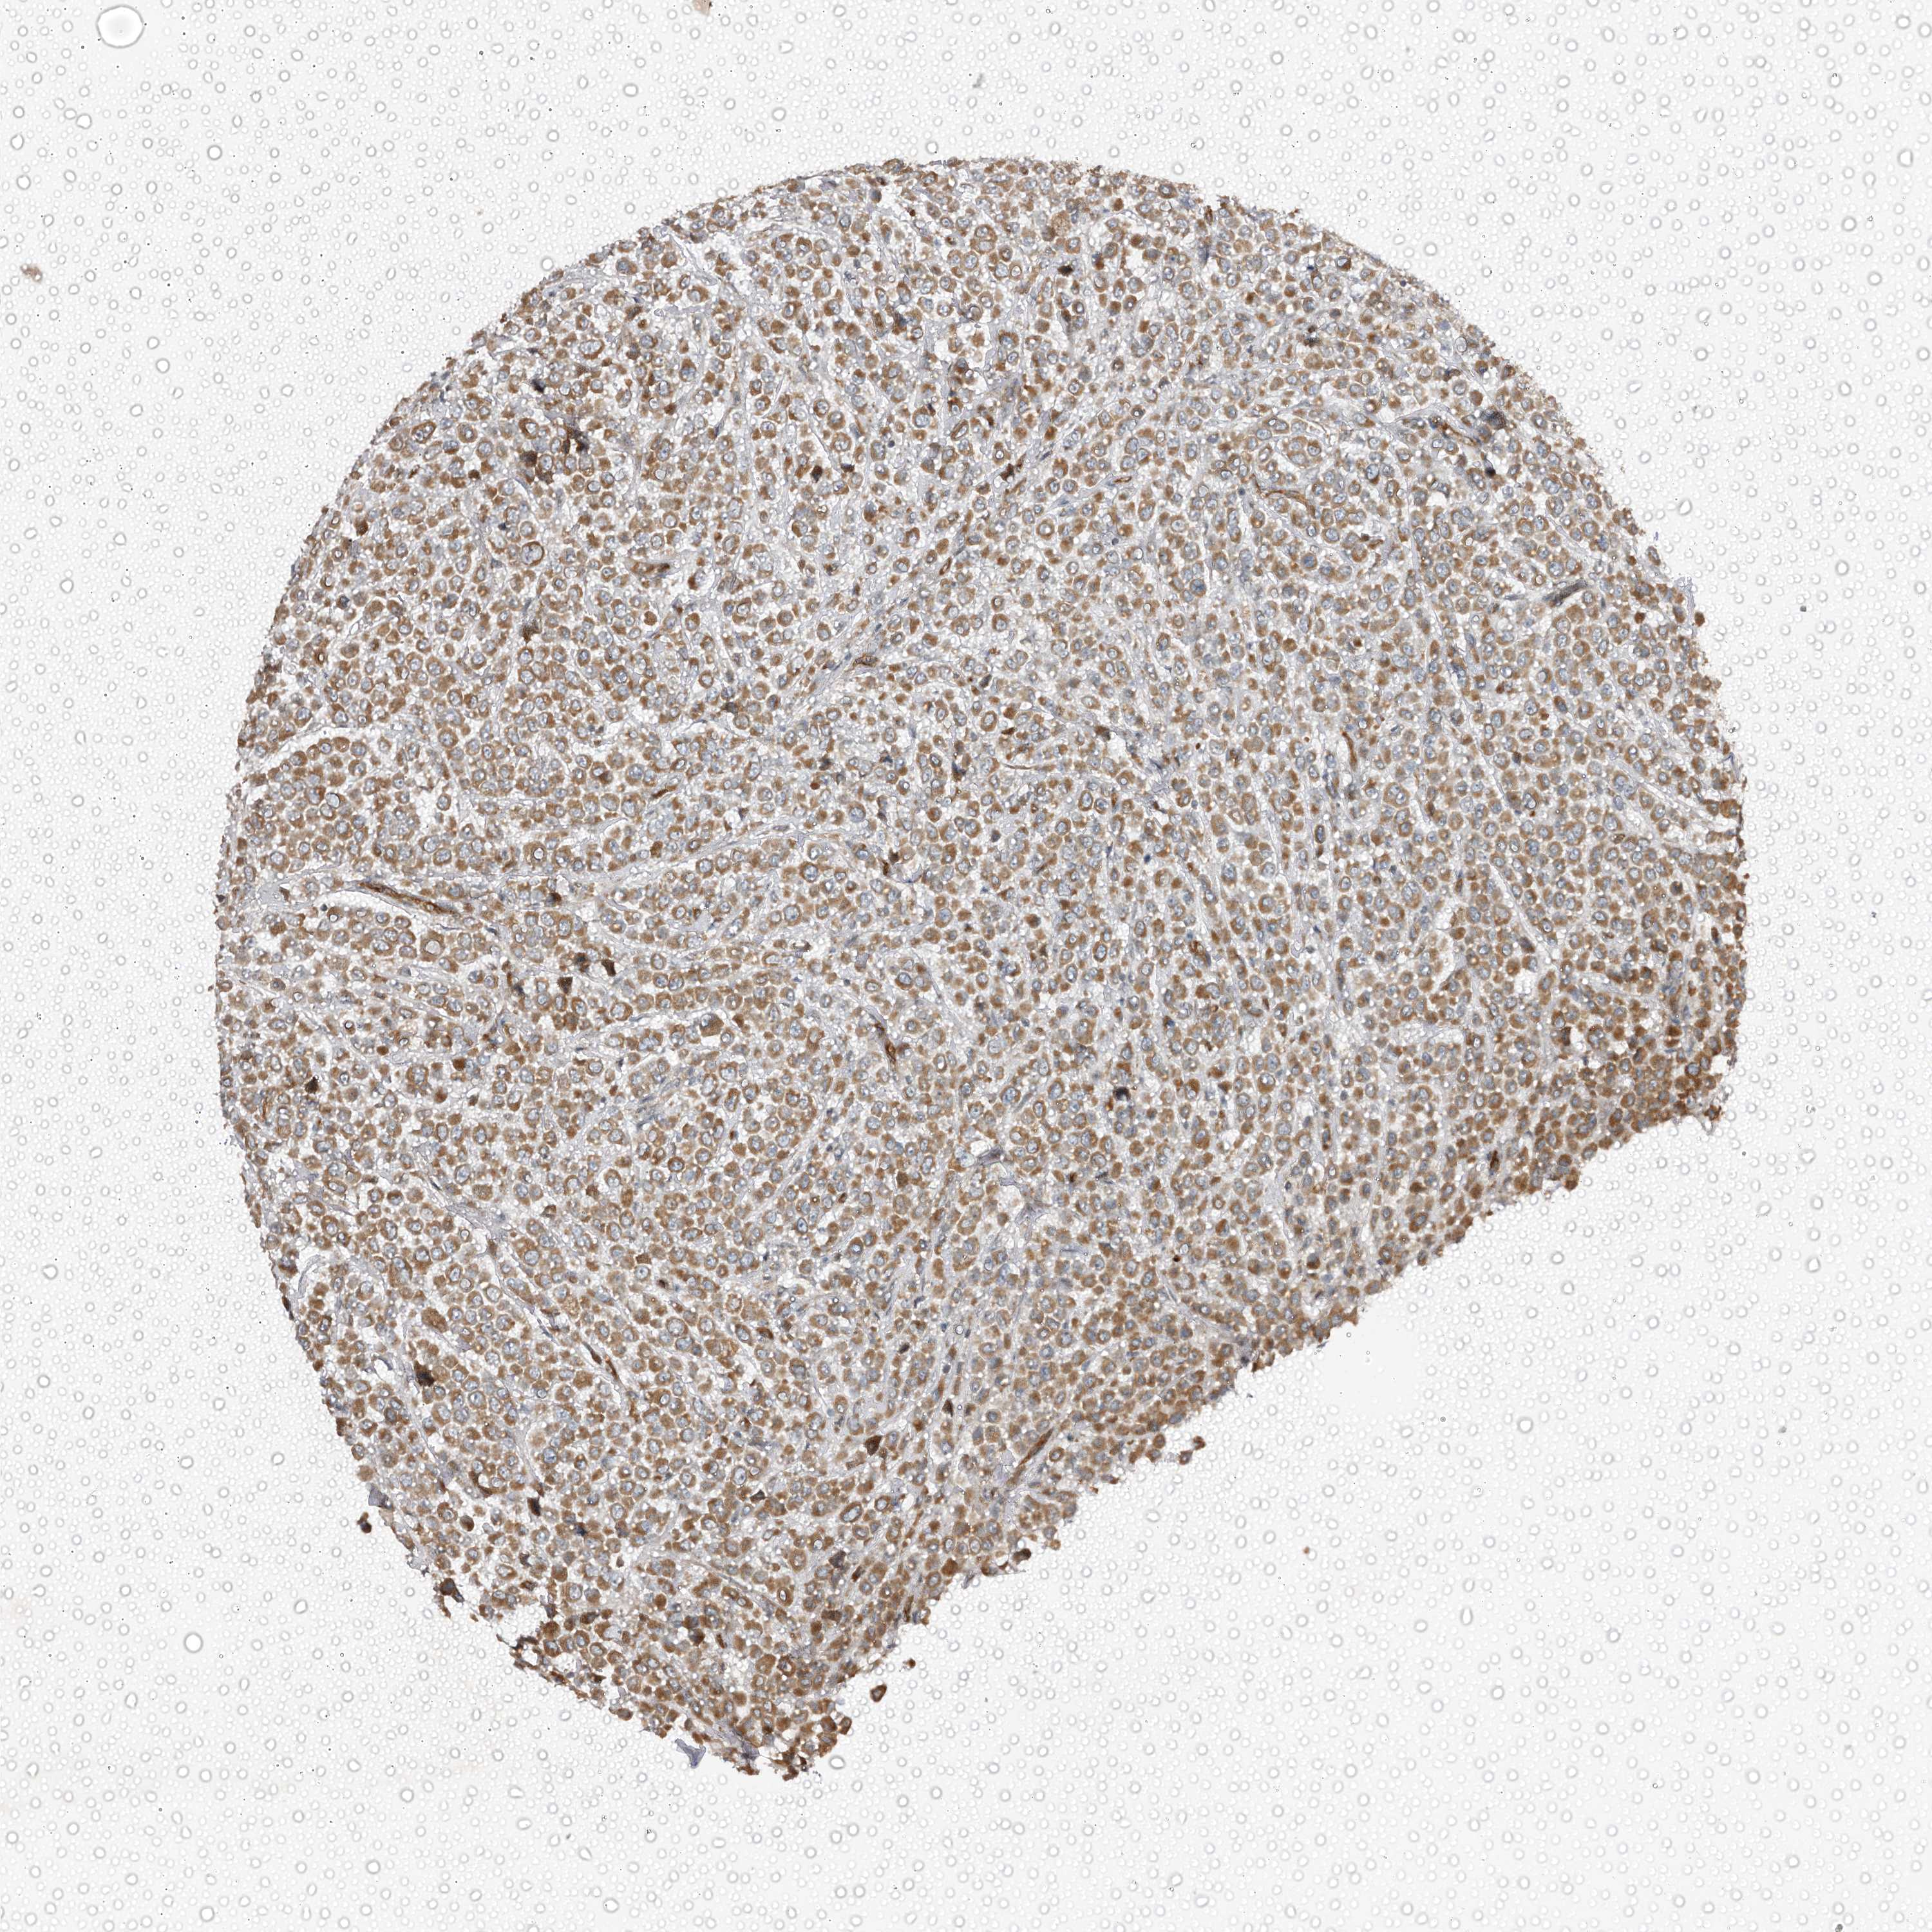

CANCER BREAST CANCER Show tissue menu

BRCA TCGA BRCA VALIDATION PROTEIN EXPRESSION